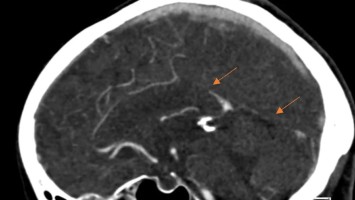

58-Jährige mit neurologischen Beschwerden – ist eine frühere Schwangerschaft schuld?

Seit zehn Jahren lagen die Blutdruckwerte einer 58-Jährigen bei über 200/120 mmHg – ohne Beschwerden. Vor drei Monaten kam es plötzlich zu einer transitorischen ischämischen Attacke. Ein Blick in die Anamnese ergab: Vor 30 Jahren musste ihr Kind in der 33. Schwangerschaftswoche wegen Komplikationen geholt werden. Was verbindet dieses Ereignis mit den aktuellen Beschwerden?

Digitales Blutdruckmessgerät/© Kotchakorn / Stock.adobe.com (Symbolbild mit Fotomodell), Injektionsnadeln für Regionalanästhesie/© zlikovec / Getty Images / iStock, Reanimation/© Rea / stock.adobe.com, Langzeit-EKG mit junktionalem Ersatzrhythmus/© O. Schäfer, Fokussierter Herzultraschall (FoCUS)/© Dieter von Ow / all rights reserved Springer Medizin Verlag GmbH, Pulsoximeter wird an Finger angeschlossen/© Yakobchuk Olena / stock.adobe.com, Rhabdomyom im Kindesalter /© Höck M et al. doi.org/10.1007/s00112-025-02259-w unter CC-BY 4.0, Eine Pinzette wird vom Tisch genommen während einer OP/© JazzIRT / Getty Images / iStock (Symbolbild mit Fotomodellen), Venöse CT-Angiografie: Sinusthrombose/© Wohlfahrt L. et al. / all rights reserved Springer Medizin Verlag GmbH, Übergabesituation im Herzkatheterlabor/© Ernst M et al. / all rights reserved Springer Medizin Verlag GmbH (Symbolbild mit Fotomodellen), Frau misst Blutdruck/© Microgen / stock.adobe.com (Symbolbild mit Fotomodell), Transösophageale Echokardiographie (fTEE), 4‑Kammer-Blick/© Michels M et al. / all rights reserved Springer Medizin Verlag GmbH, Screening auf Präeklampsie/© Musik T et al. / all rights reserved Springer Medizin Verlag GmbH, Arzt nimmt Schwangeren Blut ab/© Andrey Popov / stock.adobe.com (Symbolbild mit Fotomodellen), Patient im Gespräch mit Ärztin/© sebra / stock.adobe.com (Symbolbild mit Fotomodellen), Mann hält Tablette und ein Glas Wasser in den Händen/© somenski / Fotolia (Symbolbild mit Fotomodell), Herpes Zoster am Rücken/© Mumemories / Getty Images / iStock (Symbolbild mit Fotomodell), EKG befunden mit System - EKG Essential/© Springer Medizin Verlag GmbH